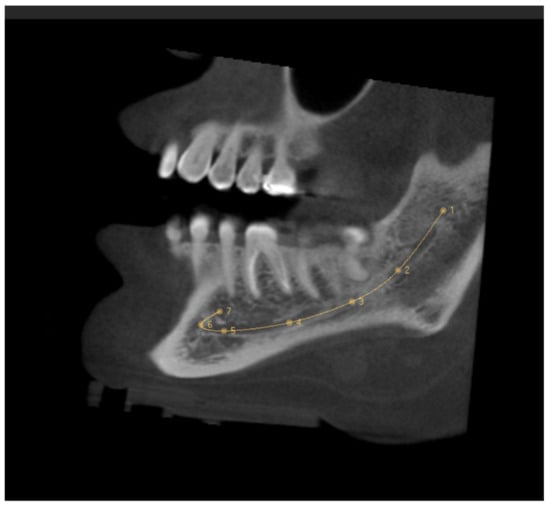

The MC was traced in the sagittal section, which made it possible to see its trajectory. First, the entry of the IAN to the MC in the MF was identified in the coronal section, setting the first reference point here. The following points were placed equidistant from each other following the course of the MC. The last point was fixed on the MF, taking the curve of the AL into account (Figure 1). It was ensured that each point was well located on all CBCT sections. The length of the MC was provided by the software after tracing the MC, and the records were taken in mm.

Figure 1. Sagittal slice CBCT image showing the tracing of the mandibular canal. The first reference point is located in the mandibular foramen, and the seventh reference point is in the mental foramen.